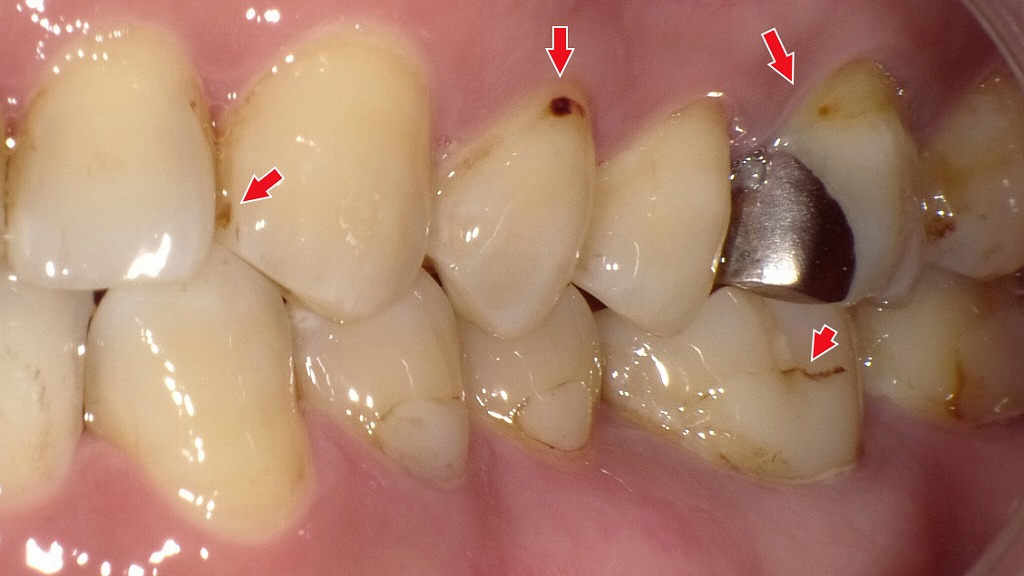

初期虫歯(C1)

初期虫歯(C1)は、虫歯がエナメル質の内部まで進行し始めた段階を指します。まだ穴は大きく開いておらず、痛みやしみる症状が出ないため、自覚しにくいのが特徴です。見た目としては、黒い点や小さな溝の変色として確認されることが多く、歯科医師による診断が重要になります。

赤矢印が示すように、歯と歯の間(コンタクト部)の初期虫歯は、肉眼ではほとんど確認できません。レントゲンを撮影することで、エナメル質内部の透過像として虫歯を早期に発見できます。見た目に穴がなくても進行している場合があるため、定期的なレントゲン検査は非常に有効です。